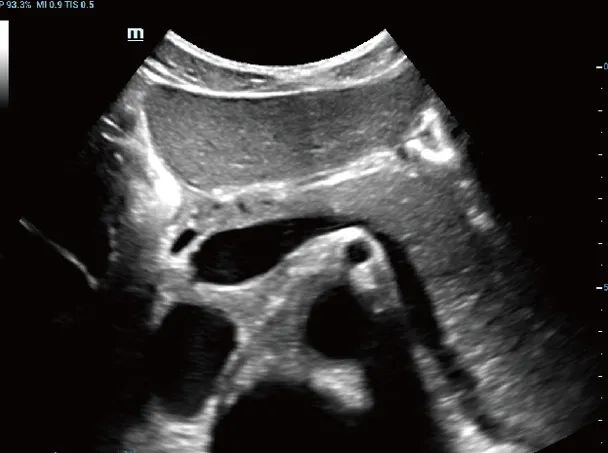

影像图

胰腺